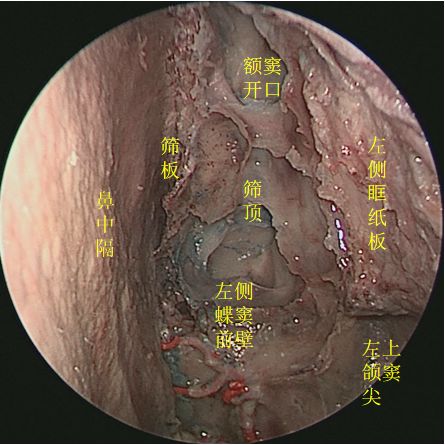

↑ 去除鼻中隔,向上方观察筛板

去除左侧筛窦,向上方观察筛顶 ↓

↑ 去除鼻中隔、左侧鼻腔侧壁结构及左眶内容物,前方观察各副鼻窦位置毗邻

去除左侧筛窦、左眶内容物,开放左侧额窦,观察额窦开口